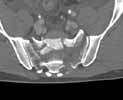

21-year old male, fall from height 8 days ago

Images attached (only CT since patient was referred to us and conventional X-rays were not digitalized).

Axial - Click to Magnify